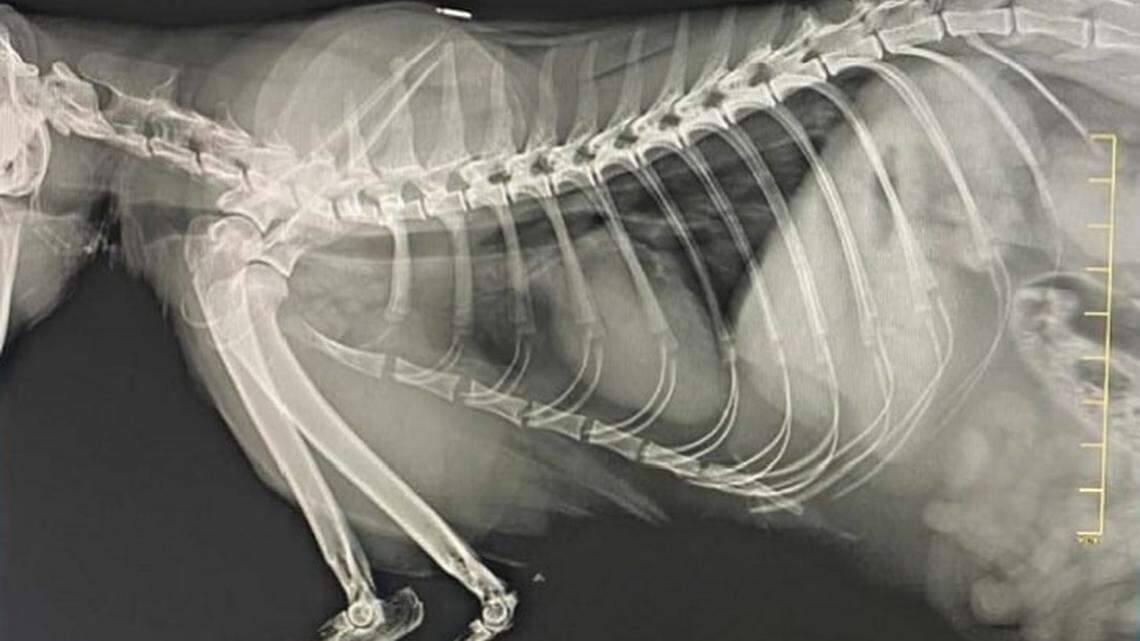

An X-ray taken on Dec. 14, 2021, at a county clinic of Piper, a cat belonging to Bronwyn Stanford, director of Animal Services for Miami-Dade. An Inspector General report found the free pet care violated county rules. Stanford, suspended since July for undisclosed reasons, denied the finding.

Later that morning, Stanford texted another administrator under her, clinic coordinator Meredith Hippert, with a question: “Anything on Piper?” Hippert texted back images of the four X-rays performed on Piper with county equipment.